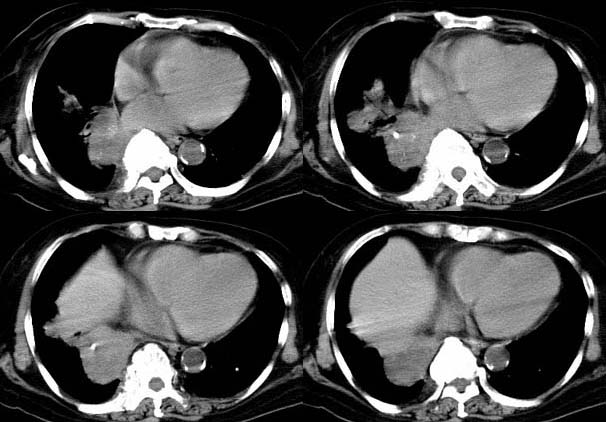

标题: CT8224女,76,咳,发热,糖尿病患者。

请大家讨论右下肺占位性质。ct值约35-55hu

右下肺癌右肺门淋巴结转移,双肺转移?建议hrct检查。

右下中央型肺癌伴右肺门淋巴结转移、右肺转移。

右肺中央型肺ca伴纵隔淋巴及肺内播散转移。

右下中央型肺癌伴右肺门、纵隔淋巴结转移,双肺肺转移

右下肺中央型肺癌伴阻塞性炎症,并右肺门淋巴结及右肺转移